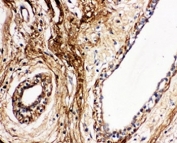

IHC-P: Protein C antibody testing of human breast cancer tissue